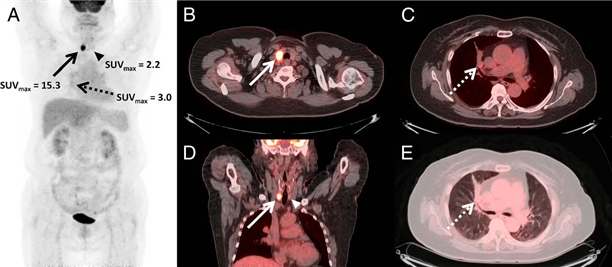

18F-FDG PET/CT 결과. 동남권원자력의학원 제공 18F-FDG PET/CT 결과. 동남권원자력의학원 제공

논문에 보고한 사례는 원발성 부갑상선 기능항진증이 의심되는 71세 여성 갑상선암 환자에게 부갑상선 99mTc-MIBI SPECT/CT를 시행한 결과, 부갑상선 선종 이외에 이미 진단된 갑상선암과 당시에 알지 못했던 폐의 병소가 관찰되어 폐암 가능성이 보고됐고, 조직 검사를 통해 소세포 폐암으로 확진됐다. 과거 SPECT/CT를 이용해 두 가지 서로 다른 종양을 발견한 사례는 보고된 바 있으나, 세 가지 종양을 동시에 발견한 경우는 극히 드물다.

이 환자에게 99mTc-MIBI SPECT/CT와 18F-FDG PET/CT 검사를 시행했을 때 소세포 폐암에서 최대 표준화섭취계수가 각각 10.7, 3.0으로 나타나 99mTc-MIBI SPECT/CT가 더 높게 측정됐다. 이는 18F-FDG PET/CT에서 잘 보이지 않는 악성종양의 진단에서 99mTc-MIBI SPECT/CT의 보완적 유용성을 보여준다.